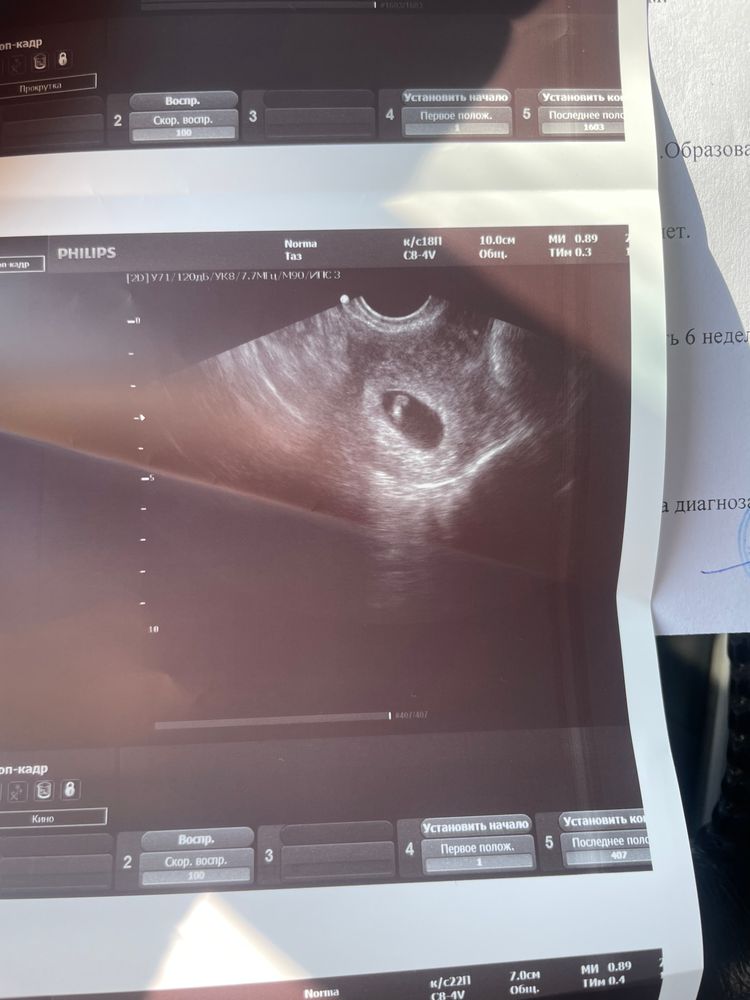

Наше первое узи😍

Ну вот и сходили на узи. Все хорошо крошка растет😍сердечко бьется ❤️В понедельник пойду к гинекологу записываться на постановку на учет. Надо быть осторожной. Тк опять шейка короткая, еще короче стала чем с младшим была.